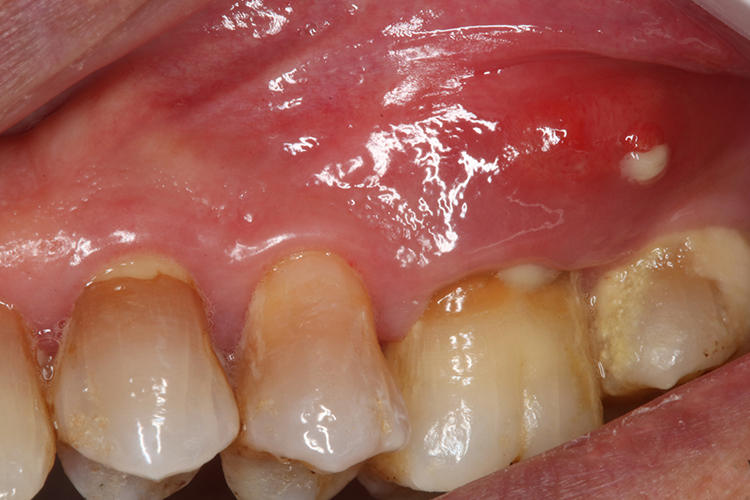

牙龈瘘管多发生于患牙根尖部或根分歧部的唇、颊侧牙龈表面,偶见远离患牙的瘘管,可以发生在患牙根尖区附近的面颊、鼻旁或颊部皮肤上。牙周袋脓肿引起的牙龈瘘管多在靠近牙颈部的牙龈位置。牙龈瘘管早期常表现为牙床上的小瘘孔,瘘孔有时封闭,有时溢脓,当根尖周脓液压力增大时,闭合的瘘孔开放,此时患牙通常出现胀痛、松动感,待脓液流出即症状缓解。